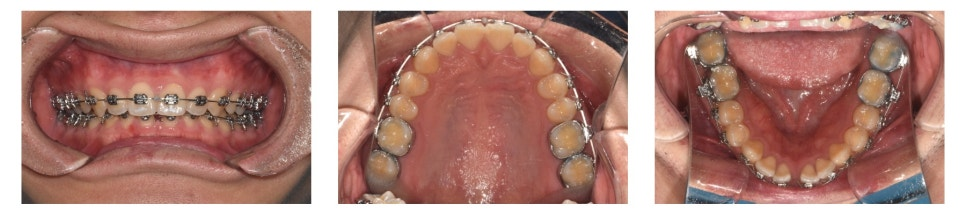

치료 시작 약 1년 후 모습입니다.

하악 중절치 사이의 공간(spacing)이 거의 닫혔고, deep bite 역시 많이 개선된 모습을 볼 수 있습니다.